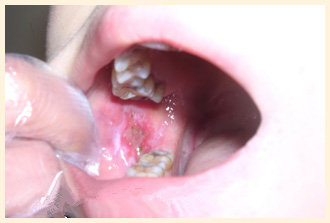

杜某,湖南人在广州市黄埔区工作,五年前吃槟榔后口腔就不舒服,口腔两边有网纹状,左颊靠近最里面板牙黏膜处有乳头状瘤,右颊红肿白色烟状斑块,有木感。碾转多家医院治疗效果不好。二年前本院诊治,经治疗四个疗程痊愈,详细见来我院治疗前后对比相片。

(杜某治疗前)

(杜某治疗后)